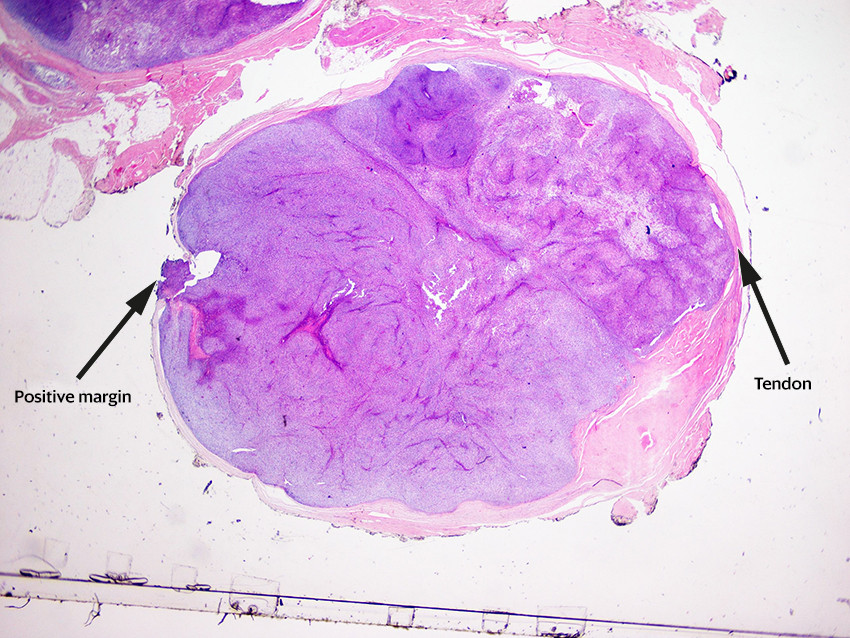

A few days later, the provisional results from pathology reported that morphology was consistent with a malignant tumour, with both synovial sarcoma and malignant peripheral nerve sheath tumour being possible differential diagnoses. There was tumour tissue at the resection margin in one small area. Immunophenotyping confirmed that the patient had a synovial sarcoma, French malignancy grade 3 (Figures 4 and 5).